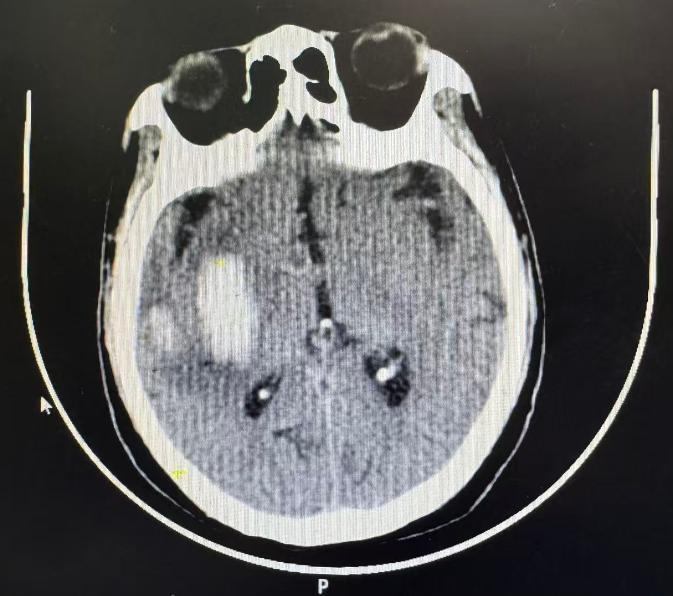

经多学科评估后,徐大叔被收治入神经康复二科。在接下来的一周里,治疗团队密切监测大叔病情变化,实时调整治疗方案 。一周后复查颅脑CT显示:出血部分吸收,出血面积较前明显减少。这份影像报告,不仅是医疗技术的成果,更是对生命坚韧的见证。